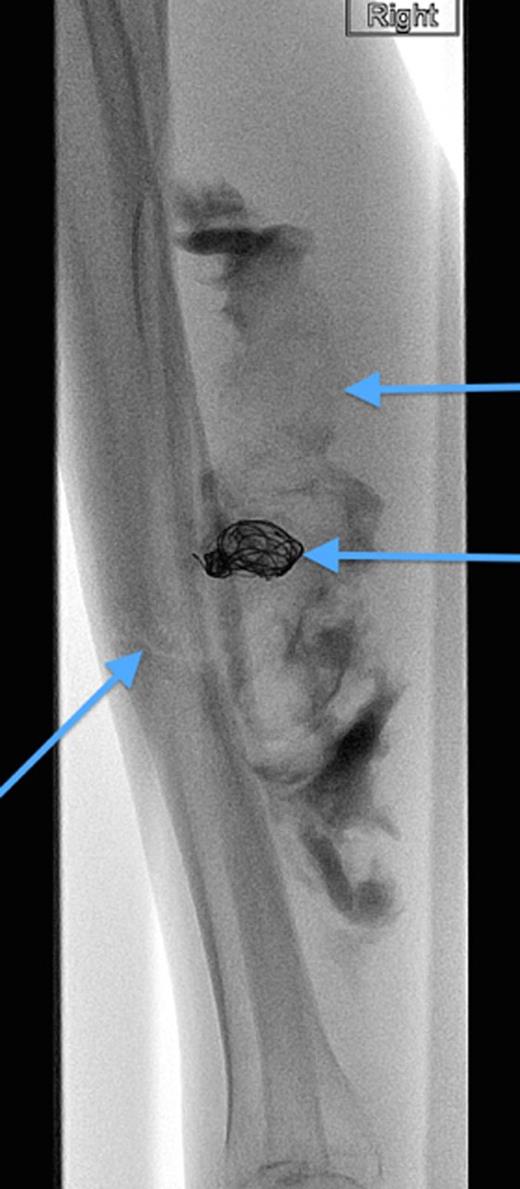

A 20-year-old man with no past medical history presented to the emergency department with non-displaced and closed transverse fracture of the left mid-tibial shaft and an intact fibula induced by a tackle during a football match. On examination, he had no neurovascular deficit and all crural pulses were palpable. His fracture was treated conservatively with a non-weight bearing above knee plaster cast later replaced by a below knee cast for a total period of 6 months. Upon examination during his attendance to the facture clinic, x-ray demonstrated no signs of fracture union. The subsequent magnetic resonance imagining (MRI) confirmed a nonunion of the fracture along with an ovoid 2.7 cm posterior compartment vascularized mass causing bowing of the interosseous septum with no evidence of avascularity of the bony margins (Fig. 1). This was confirmed to be a pseudoaneurysm originating from the PTA. An endovascular approach was adopted, and the pseudoaneurysm was injected with 2 ml of thrombin, filled with multiple coils and deployment of an angiography balloon (in the sac) (4 mm × 6 cm) for 7 min (Fig. 2). This resulted in complete cessation of the pseudoaneurysm with normal flow in the PTA (Fig. 3). The residual extravasated hematoma was later drained by an open approach. Follow-up x-ray (6 months) demonstrated complete union of the fracture site with no associated complications.

Angiographic image, demonstrating the site of the nonunion, coil insertion to the pseudoaneurysm and extravasated contrast.

Complete resolution of the pseudoaneurysm and confirmed patent PTA.